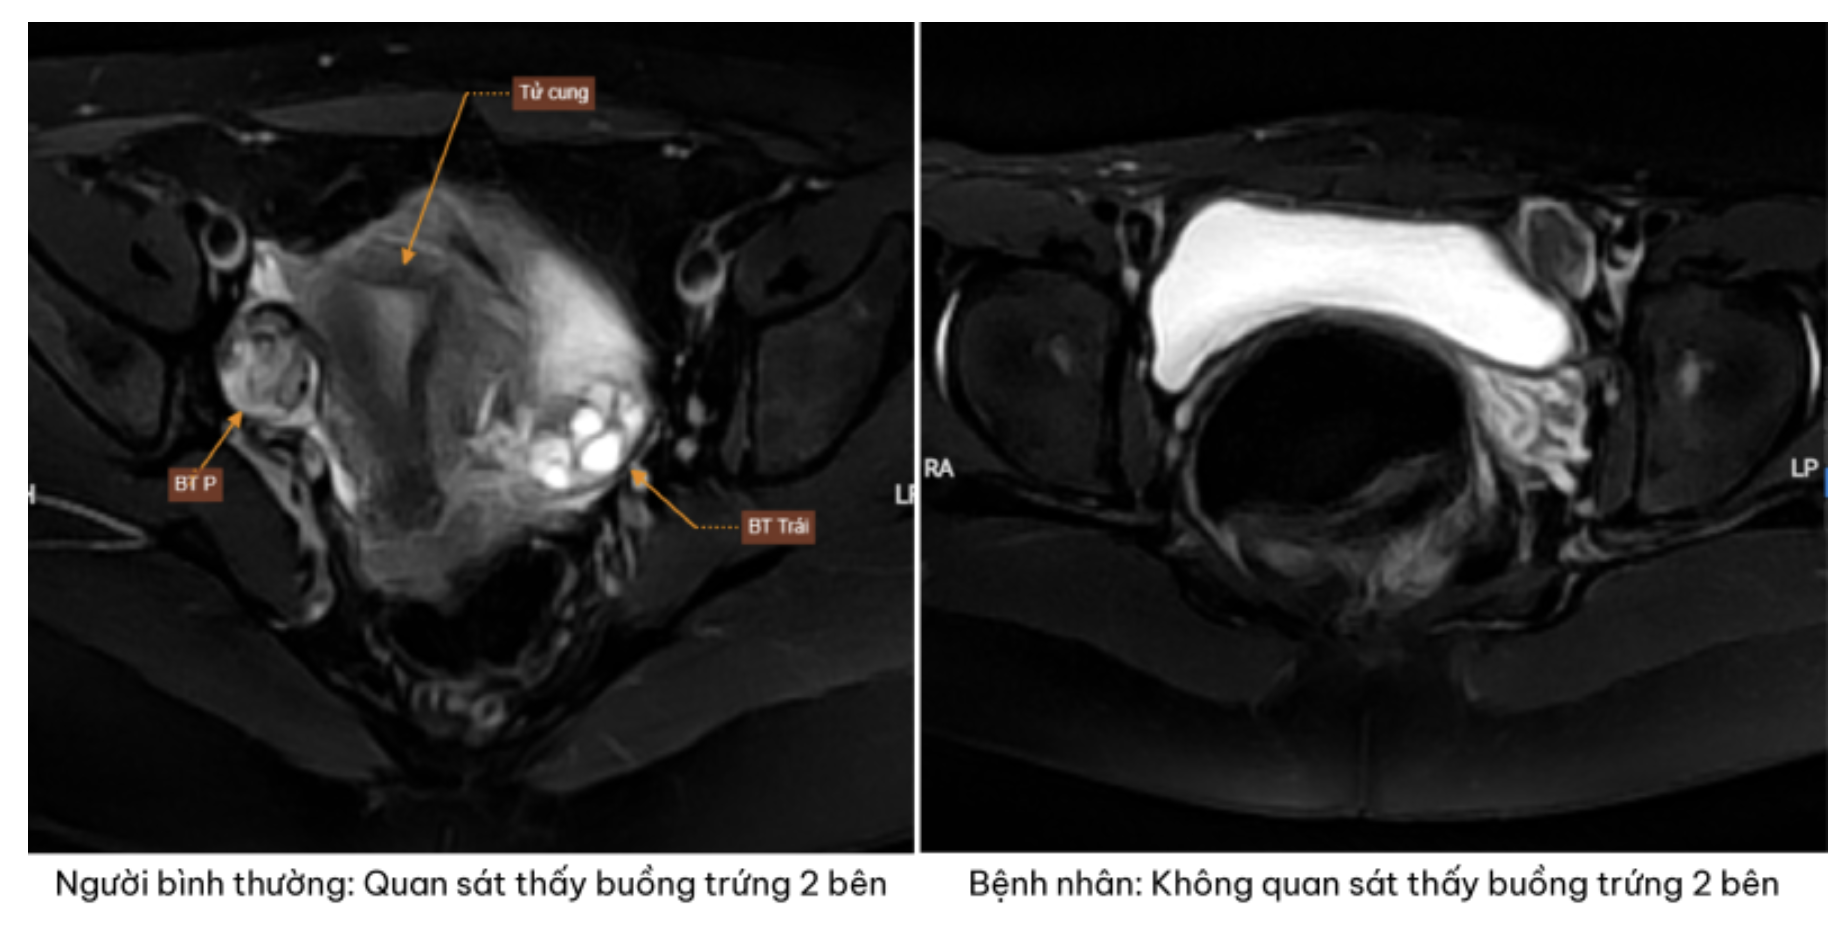

Trên hình ảnh chụp cộng hưởng từ phát hiện bệnh nhân không có tử cung và buồng trứng hai bên – Ảnh: BVCC

Kết quả siêu âm và chụp cộng hưởng từ cho thấy một thực tế khiến cả gia đình bàng hoàng không phát hiện hình ảnh tử cung và buồng trứng ở cả hai bên.

Thay vào đó, tại vùng hạ vị xuất hiện các khối tổ chức nghi ngờ là tinh hoàn lạc chỗ. Đây là dấu hiệu gợi ý đến một rối loạn phát triển giới tính hiếm gặp.